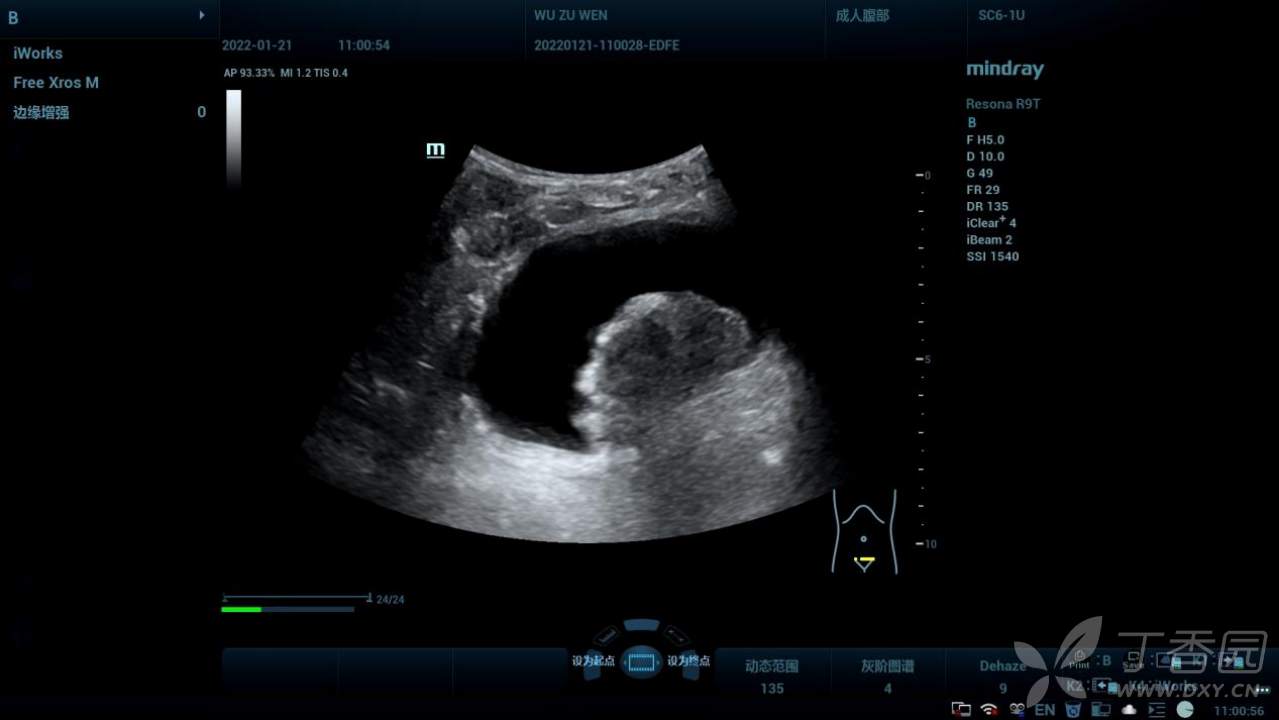

二维超声声像图:

膀胱后壁偏左侧见实性占位,边界凹凸不平,内回声不均。